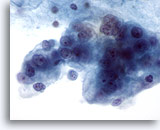

Figure 29

Breast FNA, Ductal carcinoma in situ.

Clusters of fairly bland tumor cells are noted. A vague impression of a fibrovascular core is noted in the cell group on the right. 40x

Figure 29

Breast FNA, Ductal carcinoma in situ.

Clusters of fairly bland tumor cells are noted. A vague impression of a fibrovascular core is noted in the cell group on the right.

40x